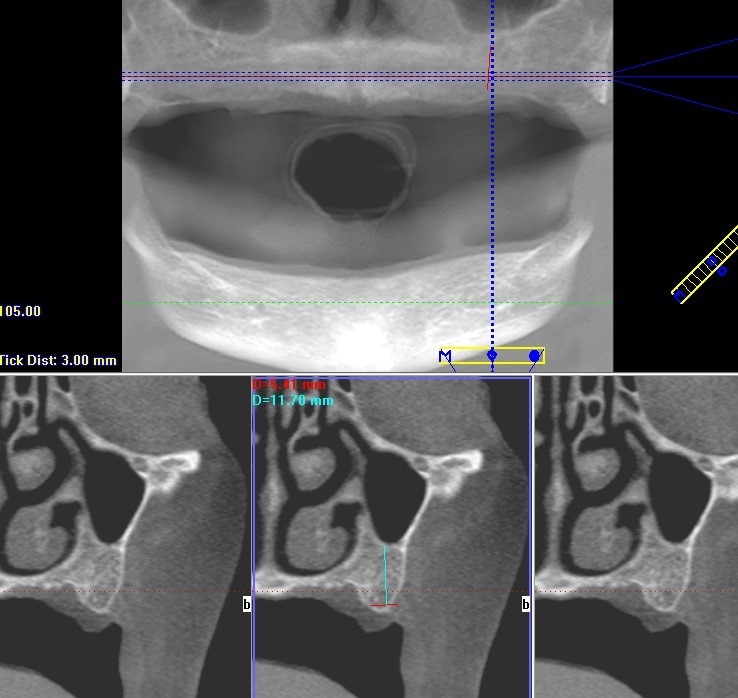

Comme nous avons planifié la pose des implants un scanner 3D (CBCT - Cone Beam Computed Tomography) a été réalisé pour examiner l'état de l’os en 3 dimensions avant l'implantation. Basé sur le scanner, on a constaté qu’il y avait suffisament d’os (hauteur et épaisseur aussi) pour pouvoir poser les implants sans greffe osseuse (pour pouvoir poser une prothèse dentaire fixe il faut poser au moin 6 implants par mâchoire). La stabilité primaire des implants à l'implantation était supérieure à 30 Ncm, donc les implant ont été fermés avec des vis de cicatrisation par le Dr Suba après la chirurgie. Si la stabilité primaire de l’implant à l'implantation est inférieure à 30 Ncm, une vis de couverture plate est placée à l'intérieur de l'implant et la gencive est complètement suturée pour une cicatrisation sans complication. Une fois la gencive au dessus des implants est complètement suturéée, une intervention chirugicale supplémentaire est nécessaire dans 3 mois pour localiser les implants et poser les vis de cicatrisation dans la gencive (healing abutments) qui la forment pour assurer un contour de gencive idéal pour les piliers définitifs.

Le scanner 3D (CBCT) montre le maxillaire et le sinus maxillaire permettant d'examiner la hauteur et l’épaisseur de l'os en 3 dimensions. Sur les 3 images inférieures on voit que l’hauteur osseuse est de 11,7 mm, qui est convenable pour la pose des implants.